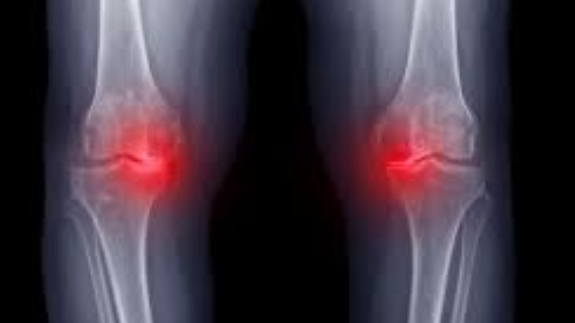

2. 관절염

정의: 무릎 관절의 염증성 질환입니다.

발생 원인: 나이, 유전, 체중, 이전의 부상 등 여러 원인에 의해 발생할 수 있는 무릎 안쪽 통증 원인입니다.

예방 및 관리: 정기적인 운동, 체중 관리, 통증을 줄이는 약물 치료 등이 있습니다.